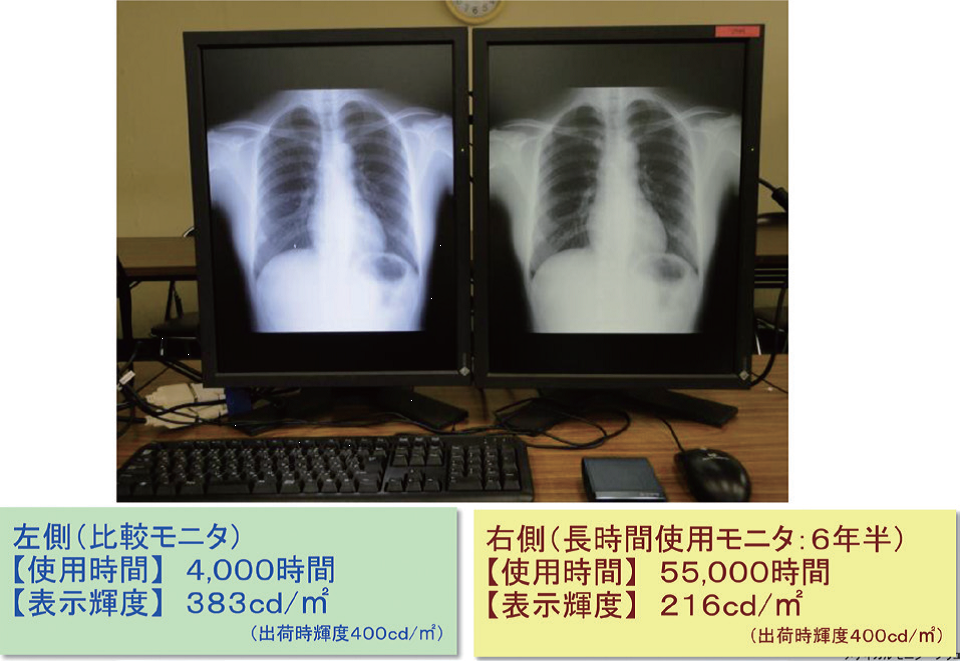

LEDを用いたモニタの経時劣化

モニタにも経時的変化があり、主にバックライトの劣化とモニタ表面の劣化がある。バックライトの劣化は、直接輝度の低下につながり、輝度は濃度分解能に影響するため、不変性試験を実施し表示精度を維持していかなければならない。デジタルマンモグラフィ品質管理マニュアルでも、モニタの品質管理が挙げられている。

その結果、輝度の低下によるファントム画像の点数の変化は大きくなかったが、一部の石灰化や腫瘤がぼけて正しく認識できない恐れがあった。また、高輝度領域では白い部分の粒状性が悪くなり、高濃度乳腺で視認性が低下する可能性が考えられた。一部の症例においてはカテゴリー判定を見誤る可能性があるため、モニタ管理の重要性が示唆された。

輝度の低下は、実際の臨床画像や日常点検で気が付くことは難しいが、定量的評価で不変性試験を行うことにより早期発見に繋がるといえる。現状ではモニタの品質管理を行っていない施設も多いが、画像表示モニタの特性を理解し、知識と意識を持つこと、またモニタの品質を管理する技術を身に付けておくことが重要であると考える。